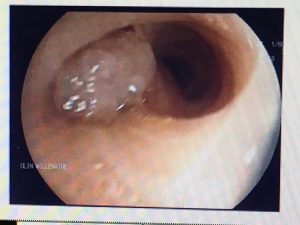

Fibroscopie bronchique: lésion bourgeonnante de la bronche lingulaire faisant suspecter une tumeur carcinoïde bronchique. Biopsies négatives.